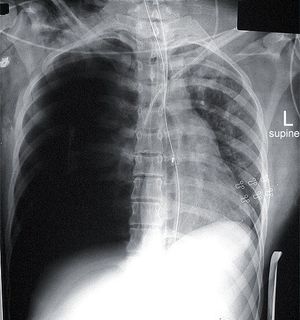

This is a supine chest image on a patient who was involved in a motor vehicle accident. There is a large right pneumothorax which is under tension. The tension has resulted in considerable mediastinal shift and there is a severe deep sulcus sign. Tension pneumothorax is a life threatening condition that results from a ball valve effect which causes air entry into the pleural space with reduced or no air out of the pleural space. As air accumulates rapidly in the pleural space with each breath. The increase in intrathoracic pressure results in massive shifting of the mediastinum away from the affected lung compressing intrathoracic vessels, which obstruct venous return to the heart. This leads to circulatory instability and may result in traumatic arrest. Non-tension pneumothorax is of lesser severity because there is slower accumulation of air and therefore slower increase in air pressure in the pleural cavity. The classic signs of a tension pneumothorax are deviation of the trachea away from the side with the tension, an increased percussion note and a hyper-expanded chest that moves little with respiration. The central venous pressure is usually raised, but will be normal or low in hypovolaemic states. Depression of the hemi-diaphragm is also seen. Treatment is one of the classic medical emergencies where life can be saved or lost on the basis of recognition and subsequent rapid decompression. Numerous techniques exist, but in the first instance relieving the tension, even if not draining the pneumothorax, is life-saving. A needle thoracostomy can be inserted, typically in the 2nd intercostal space in the midclavicular line, to gain valuable time, before a larger underwater drain can be inserted.